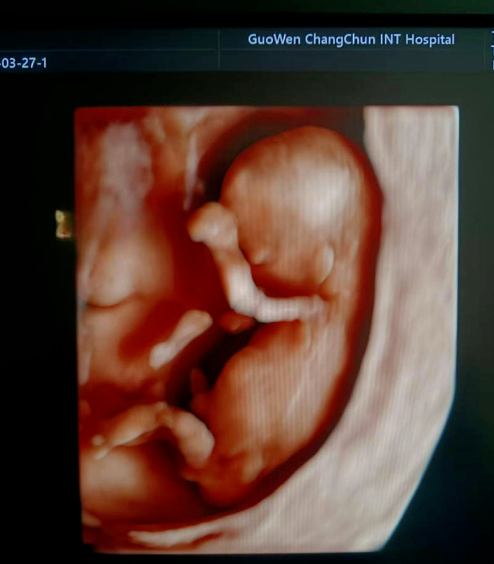

通常在懷孕 11 周 - 13 周 + 6 天之間進(jìn)行。這個(gè)時(shí)期胎兒大小適中,頸項(xiàng)透明層的顯示較為清晰,測(cè)量結(jié)果也相對(duì)準(zhǔn)確,能更好地發(fā)揮 NT 檢查對(duì)胎兒異常的篩查作用。

超聲檢查,孕婦無(wú)需空腹。檢查時(shí),超聲醫(yī)生會(huì)使用超聲儀器對(duì)胎兒頸部進(jìn)行仔細(xì)觀察和測(cè)量。通過(guò)超聲探頭可以清晰地看到胎兒在子宮內(nèi)的情況,重點(diǎn)測(cè)量胎兒頸項(xiàng)部皮下無(wú)回聲透明層最厚的部位,測(cè)量值即為 NT 值。正常胎兒 NT 值一般不超過(guò) 2.5mm。